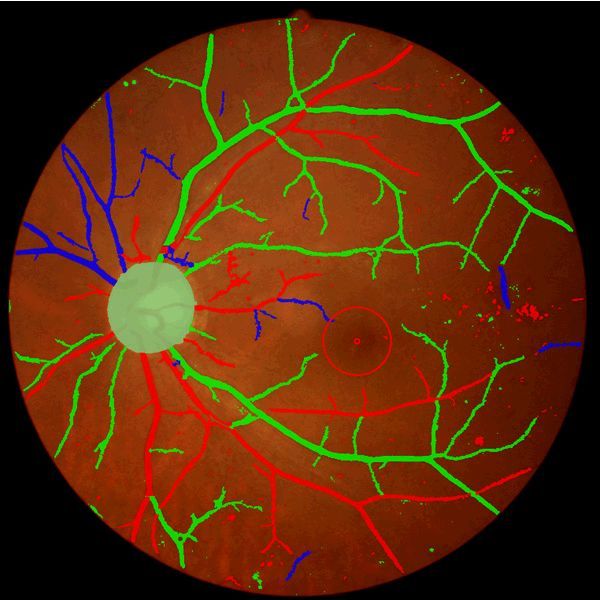

数字眼自动筛查平台

招商区域:

[全国]